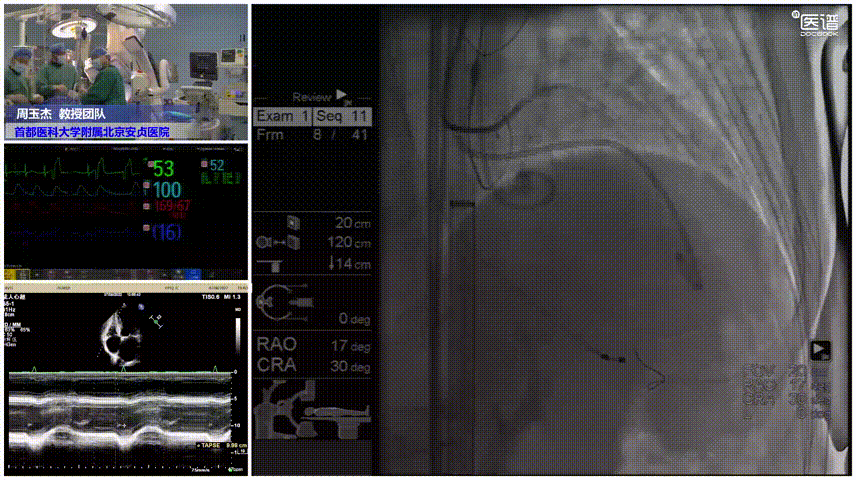

近日,在首都医科大学附属北京安贞医院纪智礼书记和张宏家院长的大力支持下,周玉杰副院长、老年心血管病中心史冬梅主任、王志坚主任、郭永和主任带领TAVR团队,在手术室、麻醉科、超声科、影像科等科室的全力配合下,成功应用TriGUARD3™抗栓塞远端脑保护装置为一名高龄低体重、严重二叶瓣畸形、重度主动脉瓣狭窄的冠脉高风险、脑梗高风险患者完成经导管主动脉瓣置换术(TAVR),术后患者恢复状况良好。这也是全球首例冠脉保护与TriGUARD3™抗栓塞远端脑保护装置同时辅助TAVR手术实施的病例。

手术过程

脑保护

患者既往有COPD病史,且体重极低,为避免麻醉相关并发症,麻醉方式上选择局部麻醉。在左侧股动脉上下两个穿刺点行股动脉穿刺,上穿刺点置入6F鞘管,下穿刺点置入8F鞘管。右侧股动脉切开处送入20F大鞘。沿左股动脉8F鞘,交换送入TriGUARD3™脑保护装置,透视下顺利过弓,准确定位后成功释放过滤器,全部覆盖主动脉弓的三条血管。经TriGUARD3™送入5F猪尾至升主动脉。